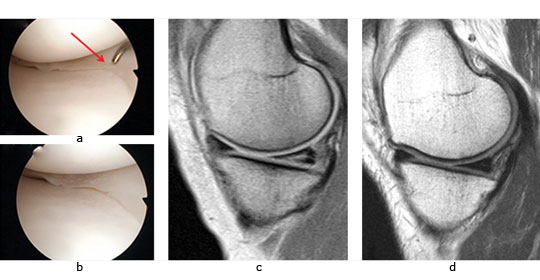

A similar approach can be used in combined chondral injuries and meniscal tears. Figure 2 shows the arthroscopic fi ndings of a 61-year-old orthopaedic surgeon and recreational skier. Two years following injury and after an unsuccessful arthroscopic debridement he was troubled by a persistent knee effusion, limited walking distance and lateral patellar maltracking with chondral lesions over the lateral patellofemoral joint. There was also an associated degenerated lateral meniscus and chondral injury in the lateral compartment. The patient underwent arthroscopic subchondral drilling together with lateral patellar release and subsequently received stem cell therapy. MRI scans at five months showed evidence of repair and regeneration accompanied with clinical improvement.

Fig. 2 Intra-operative views following subchondral drilling with the corresponding MRI scans after surgery and progressive healing at five months of the lateral trochlear, lateral femoral condyle, lateral tibial plateau and lateral patellar facet.